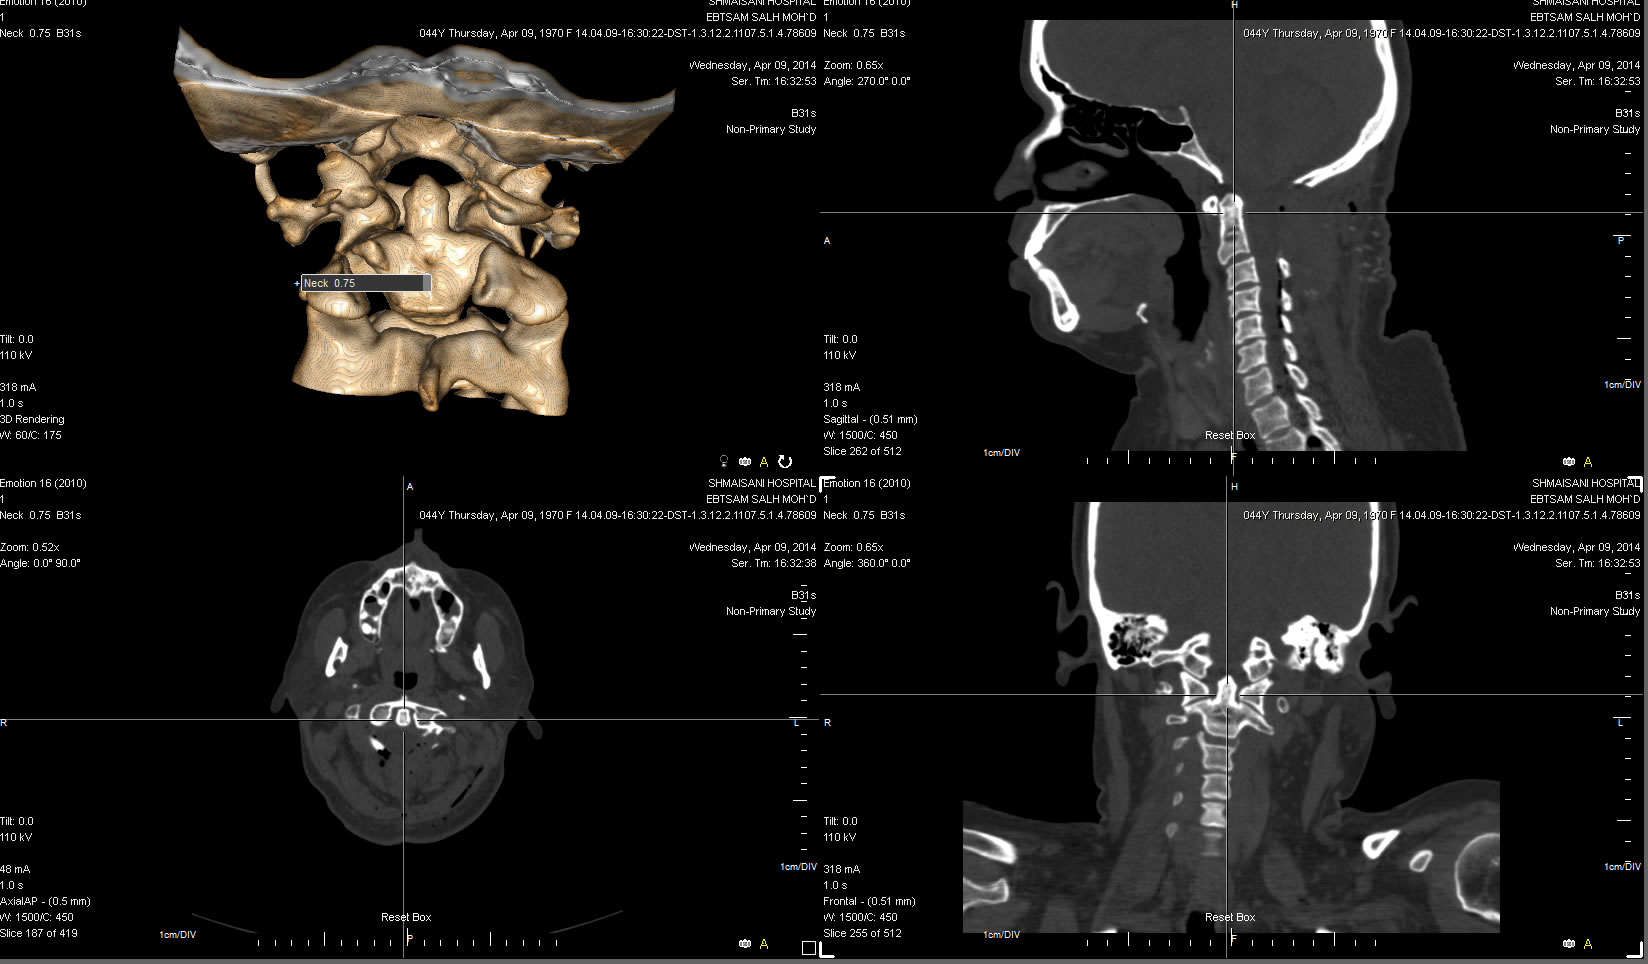

09-APRIL-2014  IBTISAM SALEH HAMAD  43 YEARS BONY TUMOR OF THE C1 LAMINA LEFT SIDE WITH SEVERE SPINAL CORD COMPRESSION.

The patient came to the clinic 10-March-2014 complaining of LBP for 18 months with right sciatica for 4 months down to all toes right foot. She has occipital headache for 1 month. MRI cervical spine done 04-March-2014 showing an osseous bony tumor originating from the left side of the C1 lamina with severe compression of the spinal cord. MRI lumbar spine showed bulge L5-S1 disc.

On examination; the patient is not limping. SLRS was 60 degrees both sides without pain. Romberg stable with no cerebellar signs. There is weak left upper limb and both feet and the proximal muscles of the left lower limb 4/5. Babinski was positive both sides. MRI of the brain with MRA ruled out presence of any connection with the vascular structures.

Setting position. Skeletonization of the foramen magnum, C1 and C2 laminae. Drilling around the lesion, which was involving the left half of C1 and C2 laminae and forming a joint between the C1 and the foramen magnum. There was a joint between the pathologically changed C1 and C2 laminae in the medial and left parts of the laminae. The drilling was continued until the dura was seen all around. Elevation of the compressing bony mass, which was adherent to the dura. Sharp dissection was done to avoid traction tear of the dura. The dura of the spinal cord after completion of the elevation of the bony mass became lax and hanging free. There was a joint between the left half of C1 and C2 laminae and between the lamina of C1 and left side of the foramen magnum. The mass was sent for histologic studies. The left C1 root was seen. The left vertebral artery was seen within its canal at the C2 level. The left C2 root was seen in the lower left corner of the created bony defect. Checking for instability with the setting position with DORO fixed clamps is impossible. Using the C-am in the lateral position with 25 degrees rotation to both sides also gave insufficient data to rule out instability. Using the C-arm in AP in the setting position also was impossible.  Further dissection of the left lateral bony parts with manual inspection gave bony continuity of C1-2 for more than 20 mm, confirming the presence of sufficient stability. Routine closure of the wound.

Smooth postoperative recovery. The power of four limbs became normal. It was decided to perform CT-scan of the area to have more confirmation about the stability of the bony structures.

Immediate postoperative CT-scan confirming the stability of the construct.

The patient has a bony mass of unusual morphology. The mass in consistency is bony hard but is different from healthy bone. It is more vascularized and having abnormal joints between the C1 and C2 laminae and the C1 and foramen magnum.

The lesion is causing clinical deterioration. May be the deformity is congenital and with age start to manifest itself. The histologic result will clear the situation.

The final histologic result confirm the presence of normal bone and bone marrow. This means, that the patient has this rare congenital anomaly.

Video showing the CT-scan reconstruction.